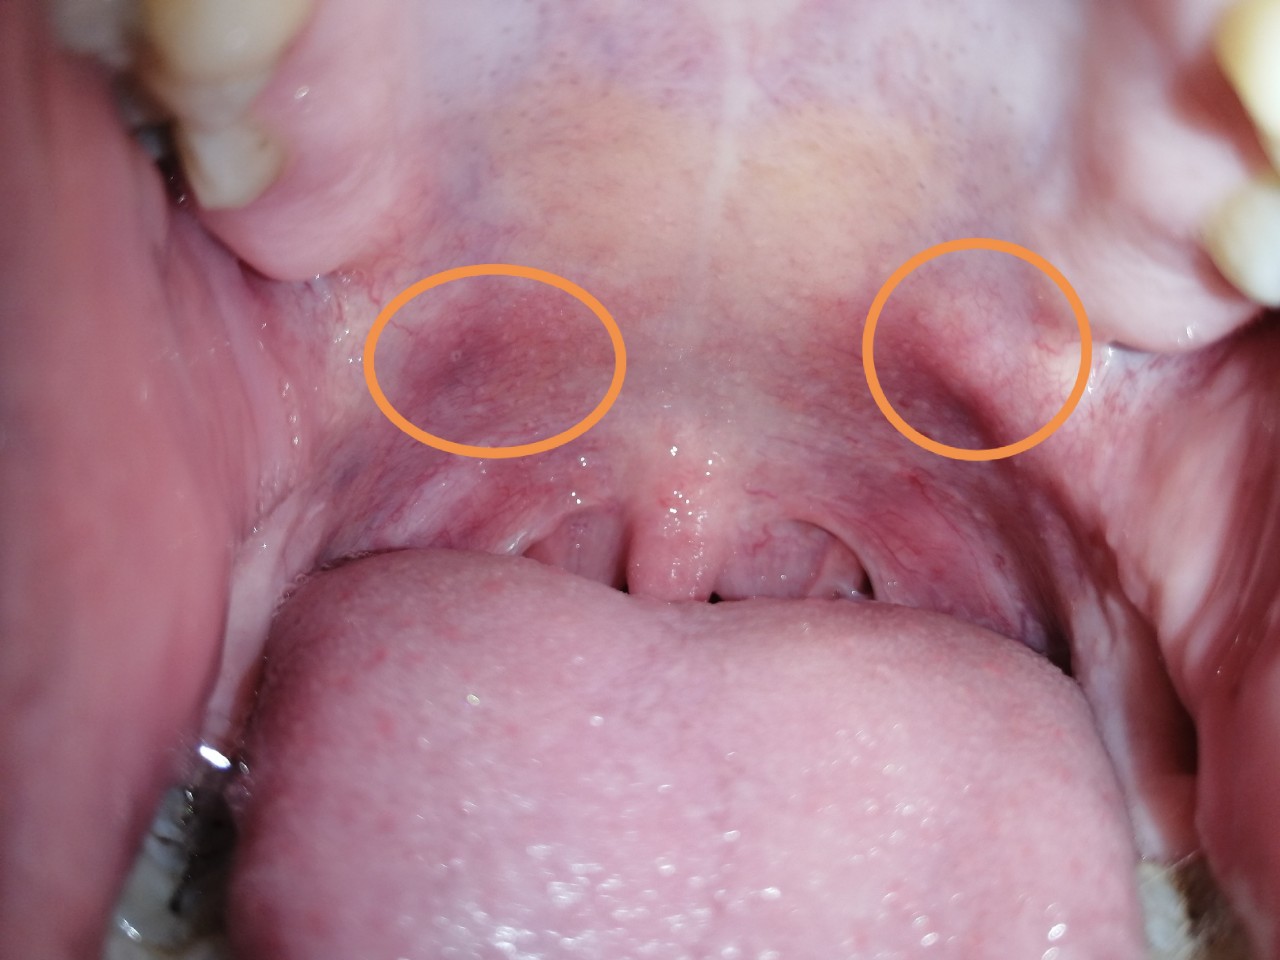

Здравствуйте, заболело горло начало отдавать в уши, поставили хронический тонзилит, фарингит, лечилась 2 месяца полосканием, антибиотики, спреями, ничего не помогает, сейчас промывают миндалины от гноя. На небной дужке все это время появилось красное пятно, бугорочек, болит. Так же на язычке неровности. Что это может быть? Очень переживаю

Пила антибионити флемоксин салютаб, пшикала люголем, гексаспреем, рассасывала таблетки имудон, фарингосепс, лизобакт, полоскала ромашкой солью содой. Миндалины промываю у врача на аппарате тонзилор. + сейчас появились 2 бугра, приносят дискомфорт, боль, фото прикладываю

Здравствуйте! Миндалины надо продолжить промывать, поскольку казеоз еще присутствует в лакунах. В остальном, используйте спрей Йокс, после которого через минут 20 полоскайте глотку раствором ОКИ 3 раза в день неделю.